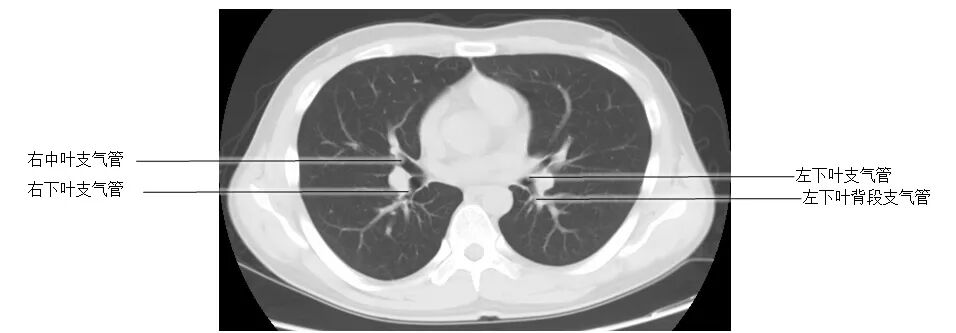

正常胸部CT影像是从横断面显示解剖和病变,可显示的结构包括胸廓、气管和支气管、肺、胸膜、纵隔和膈,CT的重建图像可从各个角度显示胸部解剖情况。不论采用何种图像显示方式,把握基本解剖结构都是必不可少的,一起学习胸部CT肺窗和纵隔窗的正常解剖。

胸部CT肺窗